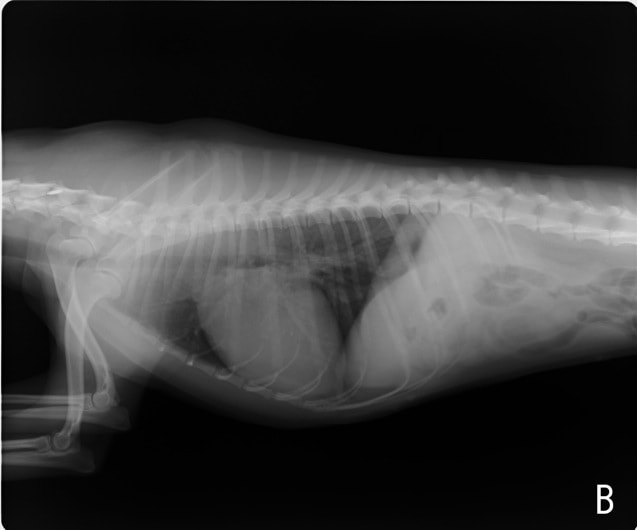

症例:【マルチーズ 12歳齢 去勢オス】

D:胸部レントゲン写真 正面像

E:胸部レントゲン写真 側面像

左側胸壁心尖部領域を最強点とするLevine 5/6の収縮期性心雑音が聴取された。

胸部レントゲン検査において重度の心拡大と肺水腫が認められた。超音波検査では、重度の僧帽弁閉鎖不全症、三尖弁閉鎖不全症、中程度の大動脈弁閉鎖不全症を合併していることが判明した。三尖弁逆流速度から肺高血圧症が示唆された。

ACE阻害薬、ピモベンダン、硝酸イソソルビド徐放剤、ベラプロストナトリウム、利尿剤としてフロセミドとスピロノラクトンを用いて治療を行った。